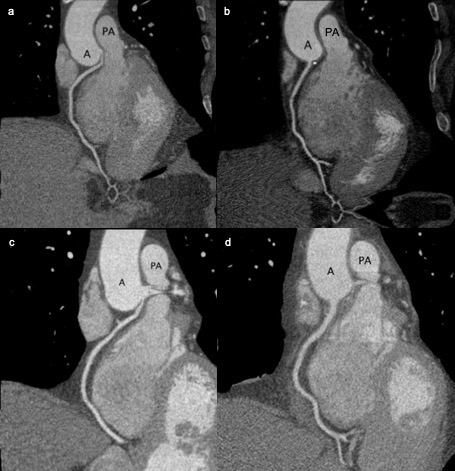

The workup for each patient began with a Lexiscan SPECT MPI stress test that showed mild inferior ischemia. Subsequent coronary artery angiograms depicted an anomalous right coronary artery originating from the left cusp superior to the left main artery take off. The malignant courses were confirmed with a coronary artery CT scan with contrast and 3D construction. A review of the coronary artery CT scan showed a malignant course of the RCA between the aortic sinus and the main pulmonary trunk, with narrowing and compression noted proximally (patient 1 imaging Figure 1a, patient 2 imaging Figure 1c). Varying partial intramural segments were also noted on CT for both patients. With the increased risk of further ischemia and shared decision-making, the patients opted to undergo open-heart surgery for reimplantation of the RCA to a trouble-free origin at the right (posterior) aortic sinus.

The two patients underwent similar reimplantation operations, both with uneventful intraoperative complications. An example procedure is outlined below, along with postoperative considerations. The surgical procedure was performed with a routine median sternotomy and pericardiotomy. Next, identification of the anomalous right coronary origin was performed with low-energy cautery and sharp dissection. Once the field was adequately exposed, heparin was given. After confirmation of activated coagulation time (ACT; 480 seconds), routine cannulation was performed, and cardiopulmonary bypass initiated. While keeping the patient warm and the heart beating, the origin of the RCA was circumferentially exposed along the right ventricle towards the right atrioventricular junction. Once adequate length was mobilized under mild hypothermia of 34 degrees C, an aortic cross-clamp was placed and cardioplegic arrest achieved using antegrade and retrograde cannulae. At this point, the RCA's most proximal end was sharply dissected as close to the aortic sinus as possible. The aortic ostial end was then closed with 6-0 Prolene in running fashion. The root was briefly filled with cardioplegia and heart filled to mark the right aortic sinus for the appropriate tension-free reimplantation location. A 5-mm diameter punch aortotomy was performed at the marked site. 6-0 Prolene suture was used to carry out a direct anastomosis of the proximal free end right coronary artery to the aorta. The patient underwent routine weaning from cardiopulmonary bypass with reversal of heparin with protamine. Perfusion of the RCA was confirmed using flow probe, which exhibited excellent flow with minimal pulsatile index (patient 1 mean coronary flow measured 53ml/min while partially on bypass with a pulsatility index of 0.8, patient 2 mean coronary flow measured 100ml/min with a pulsatility index of less than 2.5). Routine sternotomy closure was performed. In the immediate postoperative course, the patients recovered well with no complications. Both patients were extubated 2-3.5 hours after arriving in the ICU. Patient 2 exhibited ST segment elevation on telemetry in the ICU that was not validated by multiple serial 12-lead EKGs. On postoperative day 2, both patients were transferred to the step-down unit and were discharged home on postoperative day 4. The alleviation of the malignant RCA course is shown with CT angiography at three months follow up (patient 1: Figure 1b, patient 2: Figure 1d). Since the procedure, respectively 9 and 14 months ago, neither patient has reported anginal symptoms and are readmission free.

Figure 1: a. Patient 1: pre-operative CT coronary angiography that showcases the impingement of the RCA between the aorta and the pulmonary trunk. b. Patient 1: post-operative CT coronary angiography that showcases the correction of the RCA course. c. Patient 2: pre-operative CT coronary angiography that showcases the impingement of the RCA between the aorta and the pulmonary trunk. d. Patient 2: post-operative CT coronary angiography that showcases the correction of the RCA course.